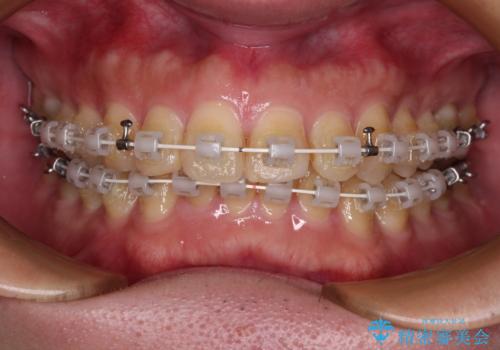

- 矯正装置

- 審美装置

- 1年4ヶ月

- 深い咬み合わせによる食いしばりで、顎関節や頭が痛むことがあるとのことで来院された患者様です。

歯ぎしりができないくらい強い食いしばりの咬合状態であったため、奥歯の歯軸を起き上がらせることで咬合を挙上させ、歯ぎしりができるようにしていくこととしました。

インビザラインでの矯正治療も可能でしたが、自己管理の煩わしさを嫌ってワイヤー装置による矯正治療を行うこととしました。